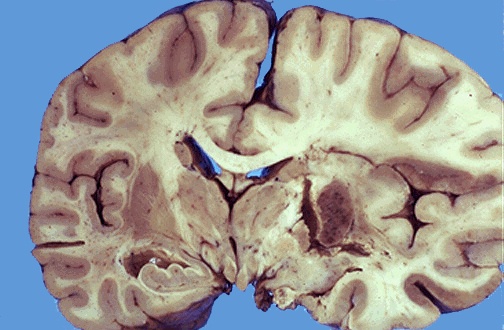

An acute cerebral infarct is seen here. Such infarcts are typically the result of arterial thrombosis or embolism. [Image contributed by Jeannette J. Townsend, MD, University of Utah]